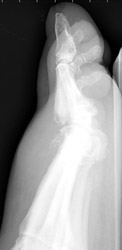

1. Distribution:

The joint contamination may be monarticular or polyarticular. Weight bearing

joints are commonly involved.

2. Erosion pattern: Soft tissue swelling and joint effusion may comprise early findings. As the infection progresses, poorly defined bony destruction with indistinct superficial marginal erosions may be evident along the articular surfaces. This may be accompanied by joint space narrowing, secondary to chondral destruction. Joint space ankylosis may occasionally occur in advanced cases.